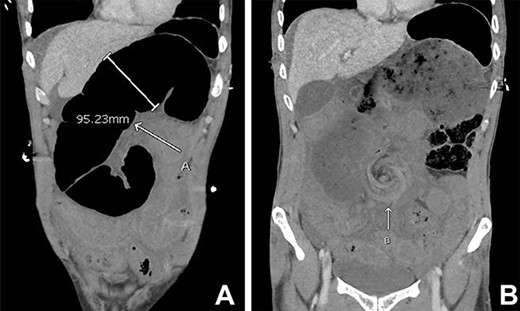

A 43-year-old man presented with acute abdominal pain, nausea and vomiting in the context of not opening his bowels for 10 days. Otherwise, he was a fit and healthy gentleman with no previous abdominal surgeries. He was a light-smoker and did not consume any alcohol or illicit drugs. On presentation, the patient was unwell with diaphoresis and had a rigid abdomen with global peritonism. Rectal examination revealed no blood or mass. Blood tests showed a raised white cell count (27.8/L), borderline elevation of lactate (2.9 mmol/L) and normal C-reactive protein (< 2.0 mg/L). Computed tomography (CT) demonstrated small bowel obstruction with multiple dilated loops with twirling of the mesenteric vessels in central abdomen, as well as moderate ascites (Fig. 1).

Initial CT abdomen pelvis with contrast in the portal venous phase showed (A) dilated small bowel and the (B) classical whirlpool sign.